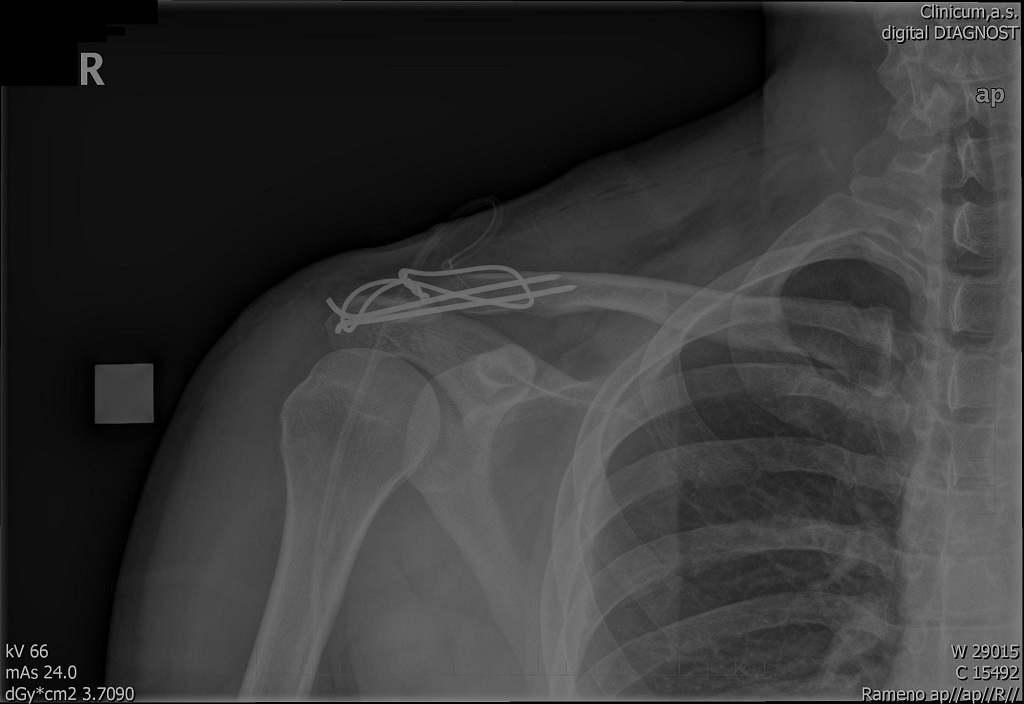

Když už sme u těch luxací AC skloubení, tak.... ;-)

nForger přiložený následující obrázek:

[125.29Kb]

to nForger: ...taky pěkná drátosmyčkaGrin Srostlé bez následků?

No když nepočítám 3 jizvy, bouli kde klíček končí a občasné lupnutí v rameni, tak v pohodě. :-) Bouli tam mám protože doktoři mi tu klíční kost přidrátovali o něco výš než měli ;-)

nForger-jojo AcéčkoGrin.Taky ho mám za sebou v roce 2007 Měsíc před odjezdem do MongolskaAngry.Takže z cesty nic nebylo.Já měl levý rameno a vykloubenej palec pravý ruky takže totální kriplGrin.Motorku jsme z kamošem zvedli a odjel jsem domu ještě 45 kmannoytakže jsem lepšíGrin.V garáži svlíknout zavolat stařku a hurá do špitálu.Tam plno tak nástup až druhej den a operace až třetí.Operoval mně brácha od kamaráda vedle z baráku kterýho jsme vždycky fackovali,protože nás pořád někde stíhal když jsme chtěli hulit a takGrin.Jinak rameno v pohodě až na pár lupnutí při výkrutech.Jo a po měsíci už jsem jezdil po okolí a za 6 týdnů po lesíchthumbs upGrin.